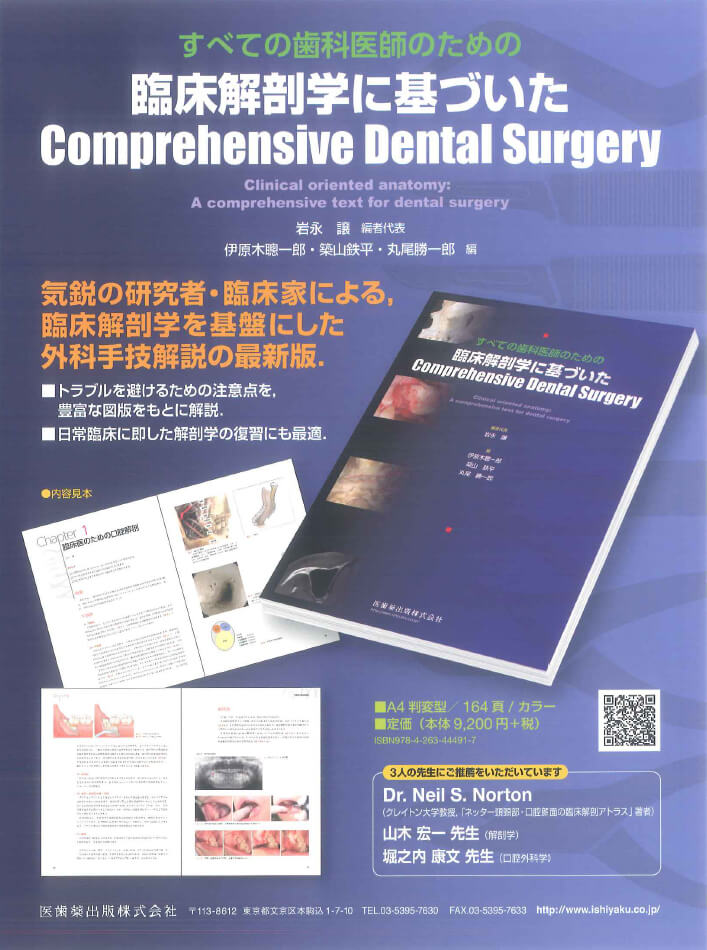

臨床解剖学に基づいたComprehensive Dental Surgery 臨床解剖学に基づいたComprehensive Dental Surgeryの詳細情報

臨床解剖学に基づいたComprehensive Dental Surgery。臨床解剖学に基づいたComprehensive Dental Surgery。Exceptional Cases Demand Exceptional Personalized Solutions。すべての歯科医師のための臨床解剖学に基づいたComprehensive Dental Surgery折れや破れは無いかと思います。薬物治療学 改訂10版。。New Clinical Protocol to Evaluate Craniomaxillofacial。8000円→7500円にお値下げしました。8月14日さらにお値下げしました。ERでの創処置 縫合・治療のスタンダード 裁断済